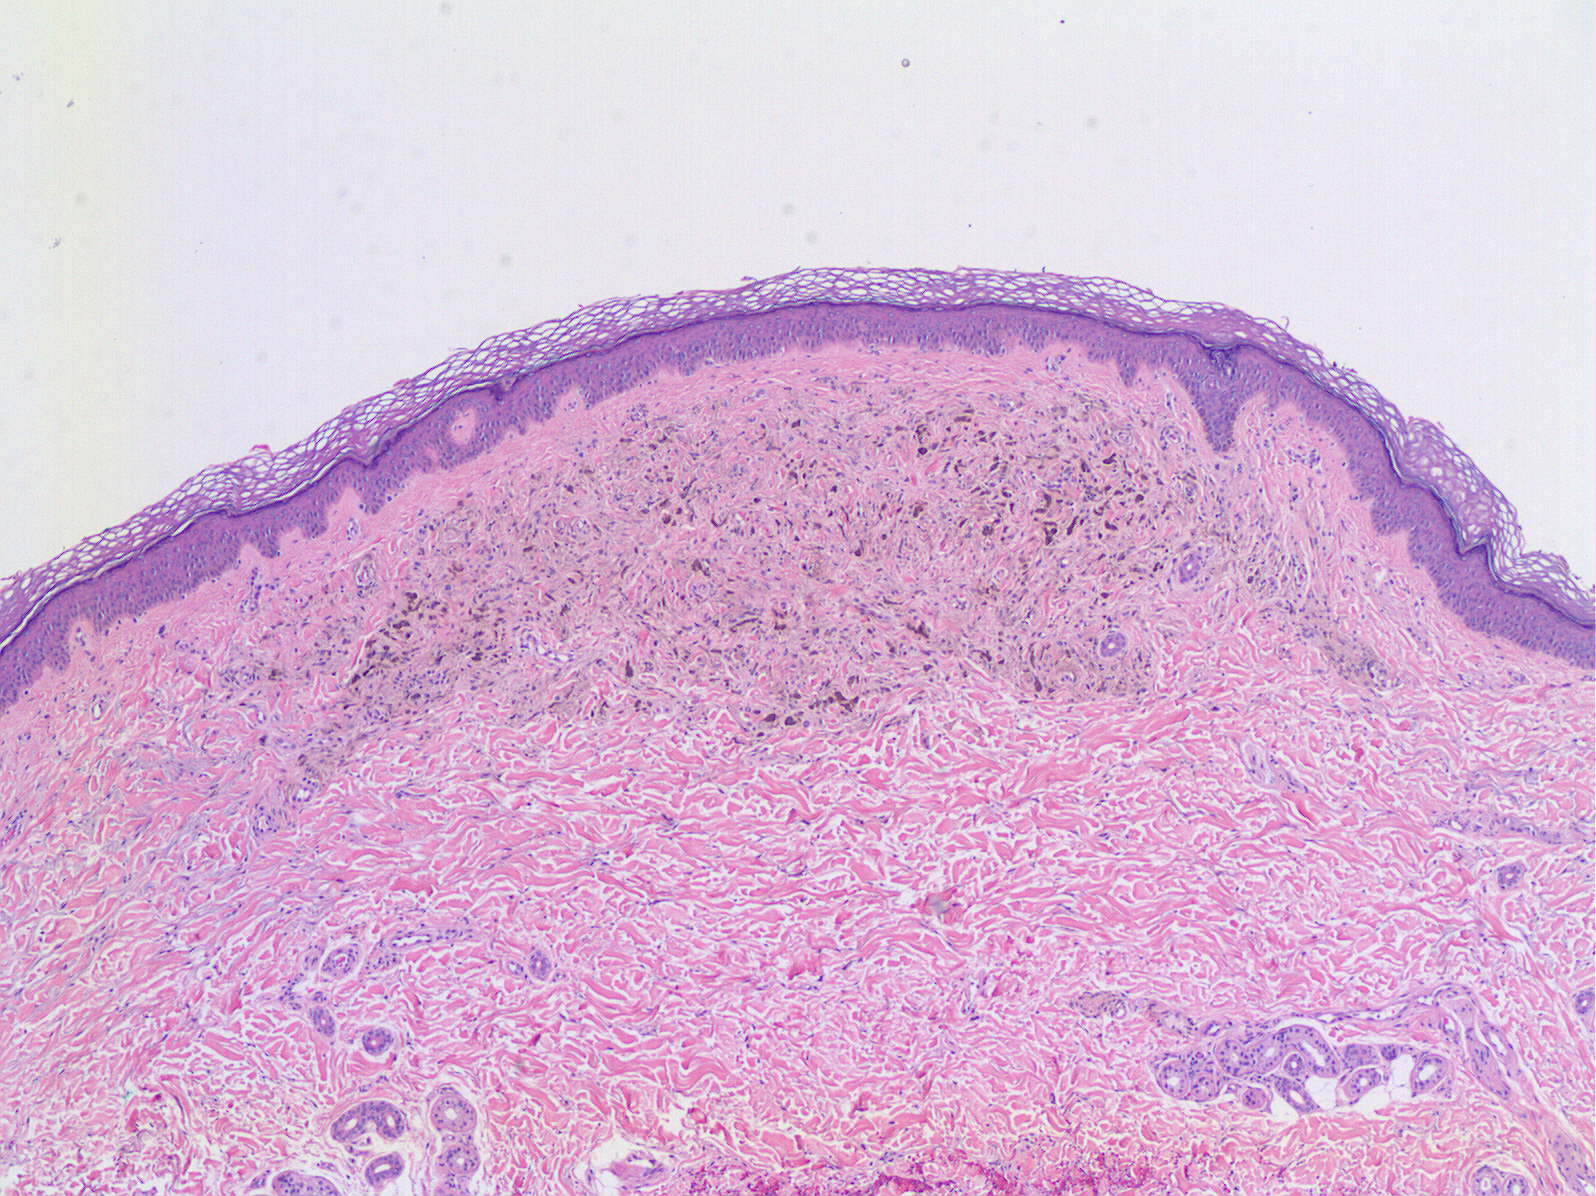

nevo usp superficial delimitada lesão derme 40x

nevo atlas usp delimitada lesão superficial derme 40x